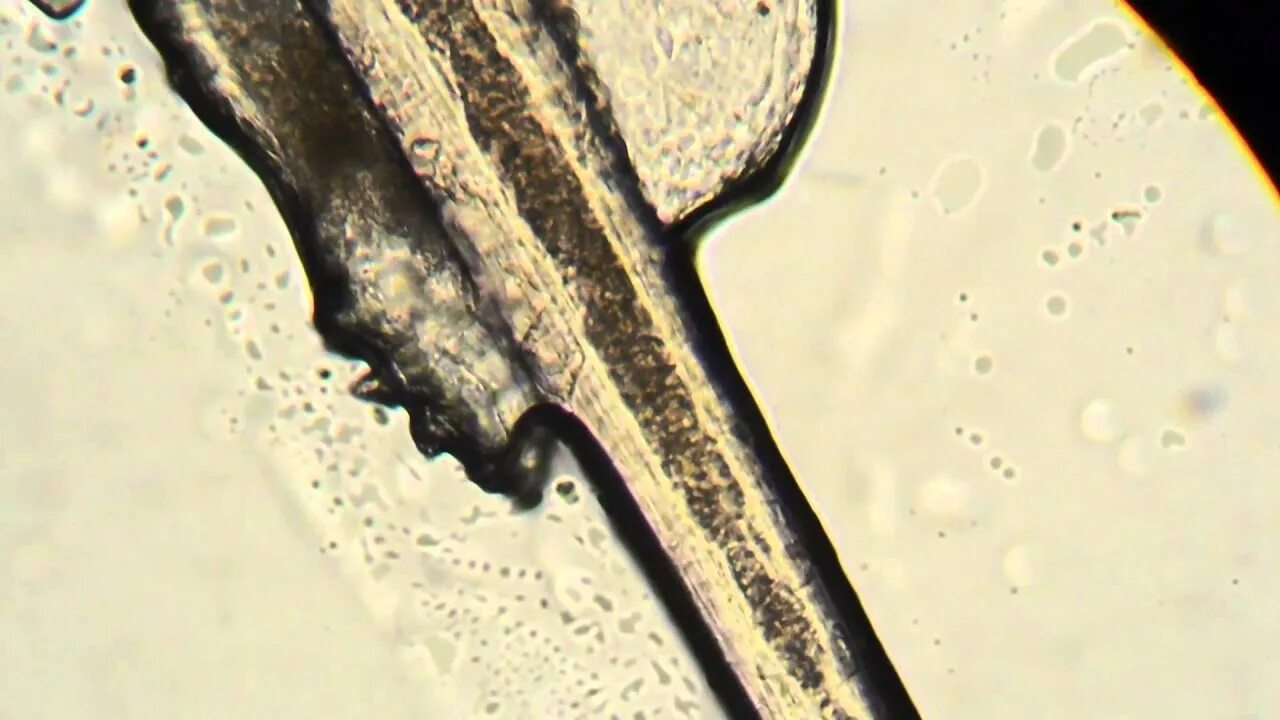

Демодекс микроскоп